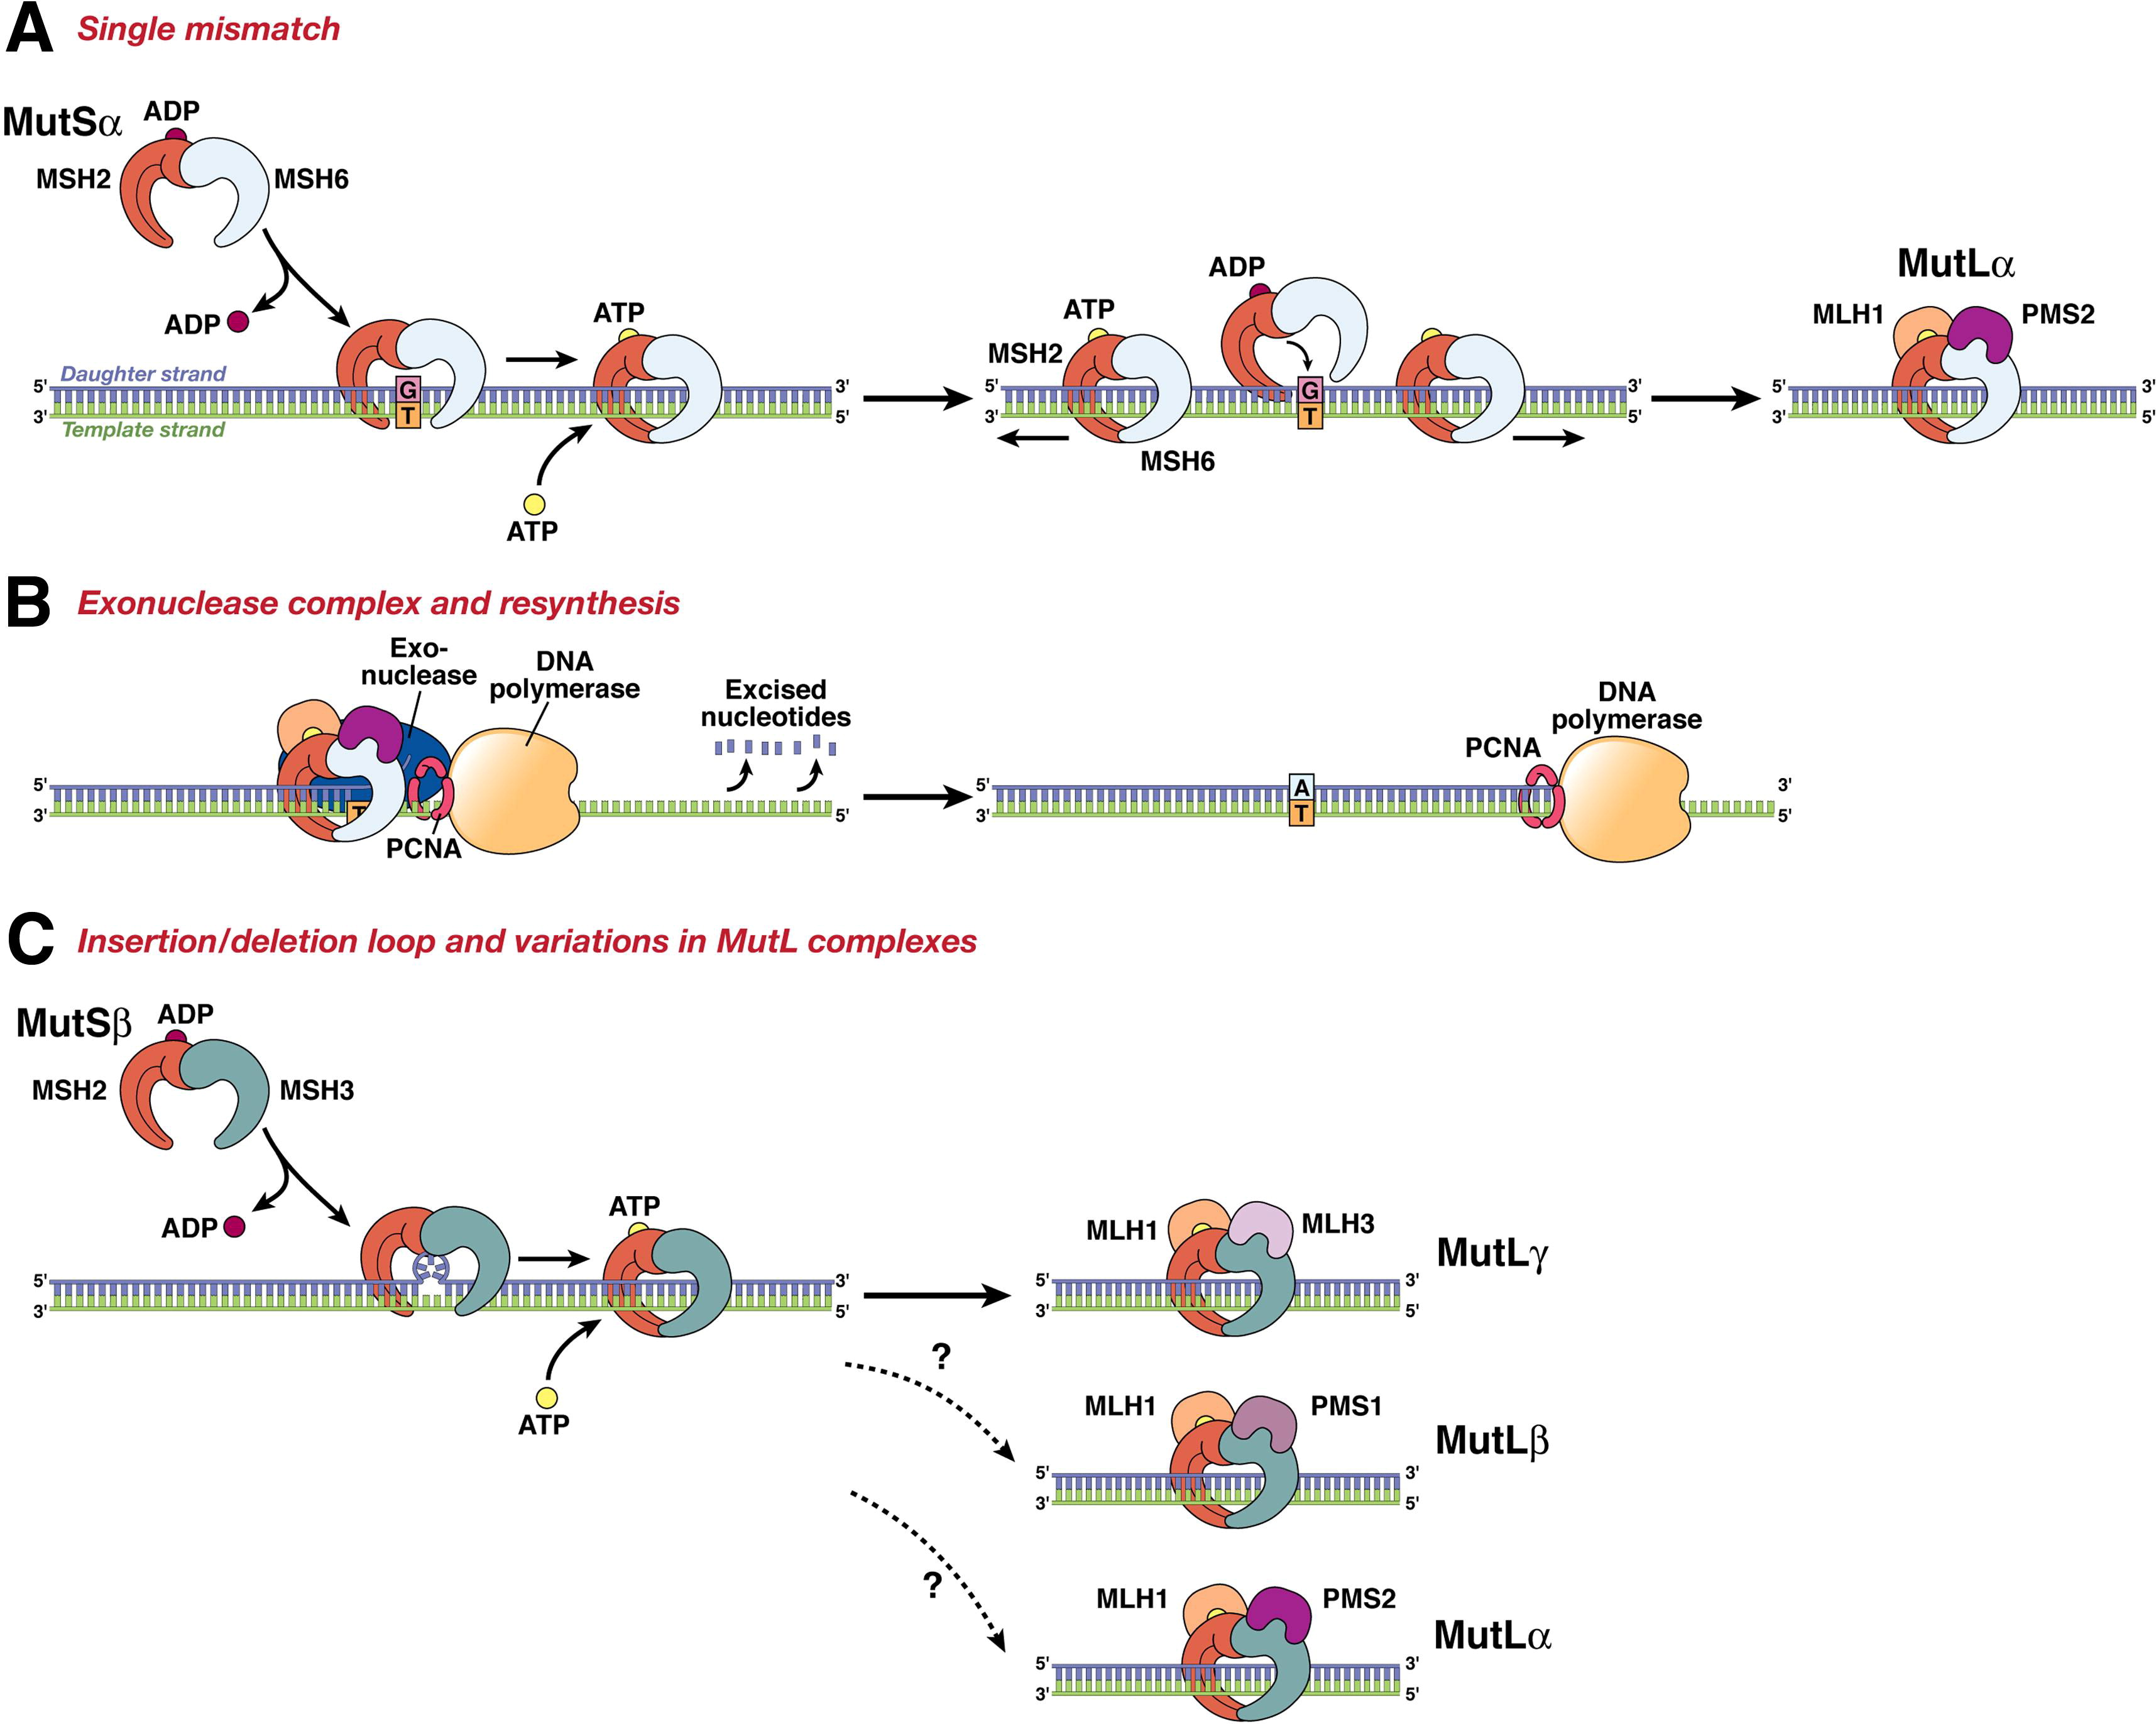

微卫星不稳定途径是由DNA修复机制缺失引起的超可变表型引起的。在具有微卫星不稳定性的肿瘤中,修复短DNA链或串联重复序列(2至5个碱基对重复序列)的能力下降;因此,突变倾向于在这些区域积累。这些突变既可以影响非编码区,也可以影响编码微卫星,当微卫星中编码的致癌基因或肿瘤抑制基因的读码框发生改变时,肿瘤就会发生。错配修复基因(MMR)的表达缺失可由自发事件(启动子超甲基化)或生发突变(如Lynch综合征中的突变)引起。这些肿瘤主要是二倍体,含有较少的LOH。在微卫星不稳定肿瘤中发生突变的基因包括MLH1、MSH2、MSH6、PMS1和PMS2[20]。一般来说,MSI肿瘤比散发性肿瘤预后好。

图8.DNA MMR系统通过一系列步骤发挥作用。(A) MSH2-MSH6 (MutSα)识别单个碱基对错配,其中DNA聚合酶将错误的碱基(G)与模板上的T匹配(左图所示),并在DNA周围产生滑动夹。这一步骤需要将三磷酸腺苷(ATP)交换为二磷酸腺苷(ADP)(由MSH2,而不是MSH6或MSH3)。该复合物从错配位点扩散,然后由MLH1-PMS2 (mutl - α)复合物结合(右)。这个“媒人”复合体沿着新的DNA链移动,直到遇到DNA聚合酶复合体。(B) DNA MMR蛋白滑动钳与核酸外切酶-1、增殖细胞核抗原(PCNA)和DNA聚合酶相互作用。这个复合体将子链切除到不匹配的位置(如图所示)。最终,复合体从DNA上脱落,重新合成发生,纠正错误。(C) DNA MMR主题的变异。虽然MSH2-MSH6识别单对错配和小idl,但MSH2-MSH3 (MutSβ)通过识别更大的idl来补充这一点(如图所示)。右侧显示了与不同的MutL二聚体可能的相互作用,因为MLH1可以与PMS2、PMS1或MLH3二聚。与MSH2-MSH3的首选相互作用是MLH1-MLH3 (MutLγ),但其他MutL异源二聚体在该反应中的确切作用尚不完全清楚 [20]。